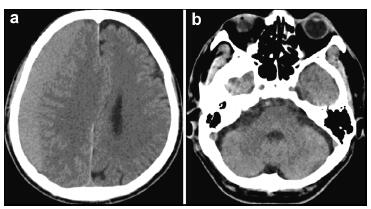

Anti-platelet therapy was suspected as a possible cause of the spontaneous occurrence of the right subdural hematoma. Preoperative coagulation parameters (prothrombin time, activated partial thromboplastin time, fibrinogen, thrombin time, and platelet count) were normal. The patient was too dysphoric to undergo surgery owing to increasing headache and confusion. Surgery was performed under general anesthesia with slight head rotation. Frontal and parietal burr-holes were drilled, followed by continuous subdural irrigation with tepid isotonic saline. The operation lasted 65 min. Perioperative blood pressure remained within the normal range. The drainage tube was connected to a closed collection system, which was fixed to the bed at the level of the patient's head. The patient's Glasgow Coma Score (GCS) improved from 12 to 15 postoperatively. A total of 220 mL, 190 mL, and 90 mL of cerebrospinal fluid (CSF) were drained from the subdural space at 24 h, 48 h, and 60 h, respectively. The patient suddenly developed nausea and vomiting, followed by deterioration of consciousness and stupor, 60 h after the evacuation. An urgent CT scan was performed, which demonstrated a significant hematoma in bilateral cerebellar hemispheres (diameter >4 cm) and a small hematoma in the frontal lobe (Figures 2a and 2b). At that time, the coagulation parameters in the blood were normal. In view of the patient's concurrent medical problems, with worsening respiratory function and poor prognosis, he was not deemed suitable for posterior fossa surgery. The patient was administered hyperosmolar therapy (250 mL of 20% mannitol every 6 h, 100 mL of 20% albumin per day), infection prophylaxis, and bed rest. The patient's GCS which was maintained at 11–12, gradually improved to 15 within 3 weeks. Repeat CT scans, which were performed 4, 7, 11, and 19 days after the operation, revealed that the bilateral cerebellar hemorrhage and frontal lobe hemorrhage had been largely absorbed (Figures 2c–2j). However, considering he had stent implantation history, it was risky to perform magnetic resonance imaging (MRI). Therefore, a preoperative CT angiography (CTA) was performed. CTA and CT venography revealed a hypoplastic right vertebral artery, and revealed dominant transverse sinus, mainly on the right side. The left side of intracranial segment of internal jugular vein and sigmoid sinus was totally undeveloped (Figure 3). The patient gradually recovered. He was discharged one month after surgery, without neurological complaints or deficits on examination.

|

| Figure 2 Computed tomography images obtained after surgery (a, b: 60 hours; c, d: 4 days; e, f: 7 days; g, h: 11 days; i, j: 19 days). |